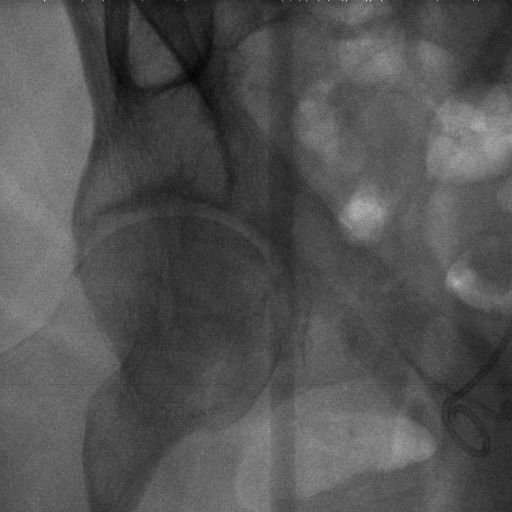

The dataset we use in the experiments is a cone-beam CT (CBCT) dataset captured for radiation therapy. The dataset contains 340 raw CBCT scans with each has 780 X-ray images. Each X-ray image comes with a geometry file that provides the registration ground truth as well as the information to reconstruct the CBCT volume. Each CBCT volume is reconstructed from the 780 X-ray images, and in total, we have 340 CBCT volumes (one for each CBCT scan). We use 300 scans for training and validation, and 40 scans for testing. The size of the CBCT volumes is 448×448×768448448768448\times 448\times 768 with 0.5 mm voxel spacing, and the size of the X-ray images is 512×512512512512\times 512 with 0.388 mm pixel spacing. During the experiments, the CBCT volumes are treated as the 3D pre-intervention data, and the corresponding X-ray images are treated as the 2D intra-intervention data. Sample X-ray images from our dataset are shown in Figure. Note that unlike many existing approaches [15, 17, 25] that evaluate their methods on small datasets (typically about 10 scans) which are captured under relatively ideal scenarios, we use a significantly larger dataset with complex clinical settings, e.g., diverse field-of-views, surgical instruments/implants, various image contrast and quality, etc.

Refer to caption

Figure 6: Sample raw X-ray images of our dataset.